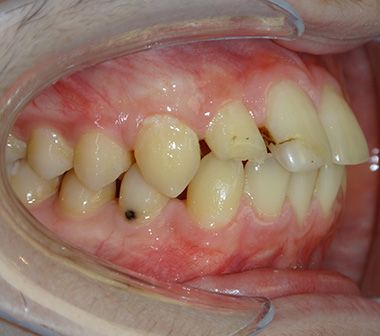

Glenn T. broke 2 teeth as a result of an accident in his childhood. These teeth were filled and the fillings were aged. Glenn was unhappy because of the gaps between his teeth. He also did not like the angle of his front two teeth. He wanted to have his teeth done before he started university. He decided to have invisalign in Turkey with his family.